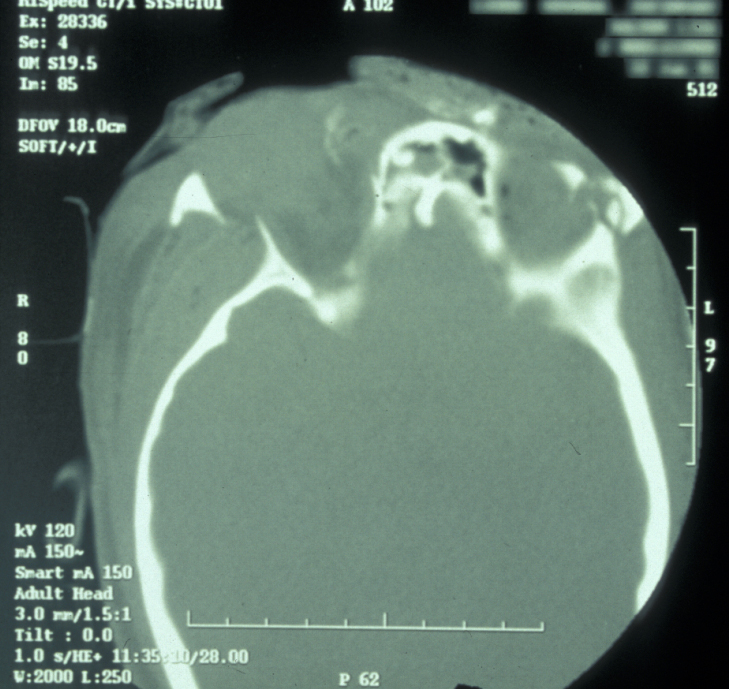

If the patient is unable to stand in the DPT machine, left and right lateral oblique mandibular views will give good imaging of the body of the mandible.  If the patient has multiple complex maxillofacial fractures a CT scan (CT coronal and axial images, with or without 3D reformatting) is helpful (see Figure 4). The CT scan will help assess condylar fracture position, angulation and any fractured dislocation of the condylar head. A CT scan is also useful to image multi-part mandibular body fractures.

Figure 4: CT scan of a displaced mandibular fracture.

Figure 5: CT scan of bilateral condylar fractures; note the overlap of fragments.